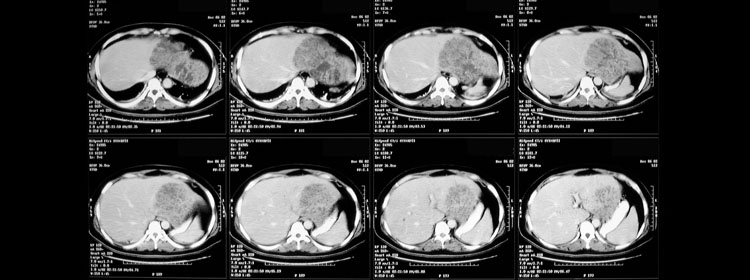

Liver cancer

Cancer of the liver is a dreaded condition affecting both young and the old. Primary cancers of the liver originate denovo in the normal liver and a also in cirrhotic livers damaged by viruses or alcohol. A Cirrhotic liver is prone to germinating cancer in its cells.

These patients present with unexplained loss of weight and appetite. They may have a vague right upper abdominal pain as well. An ultrasound and a CT will help arriving at a diagnosis. Serum CEA and alfa-feto protein levels are then checked to confirm the diagnosis.

Secondary cancers in the liver are due to primary tumours in the stomach and colon. Surgical removal of these tumours if feasible can cure these patients. Some secondary cancer deposits from colon cancer are amenable to liver resection.